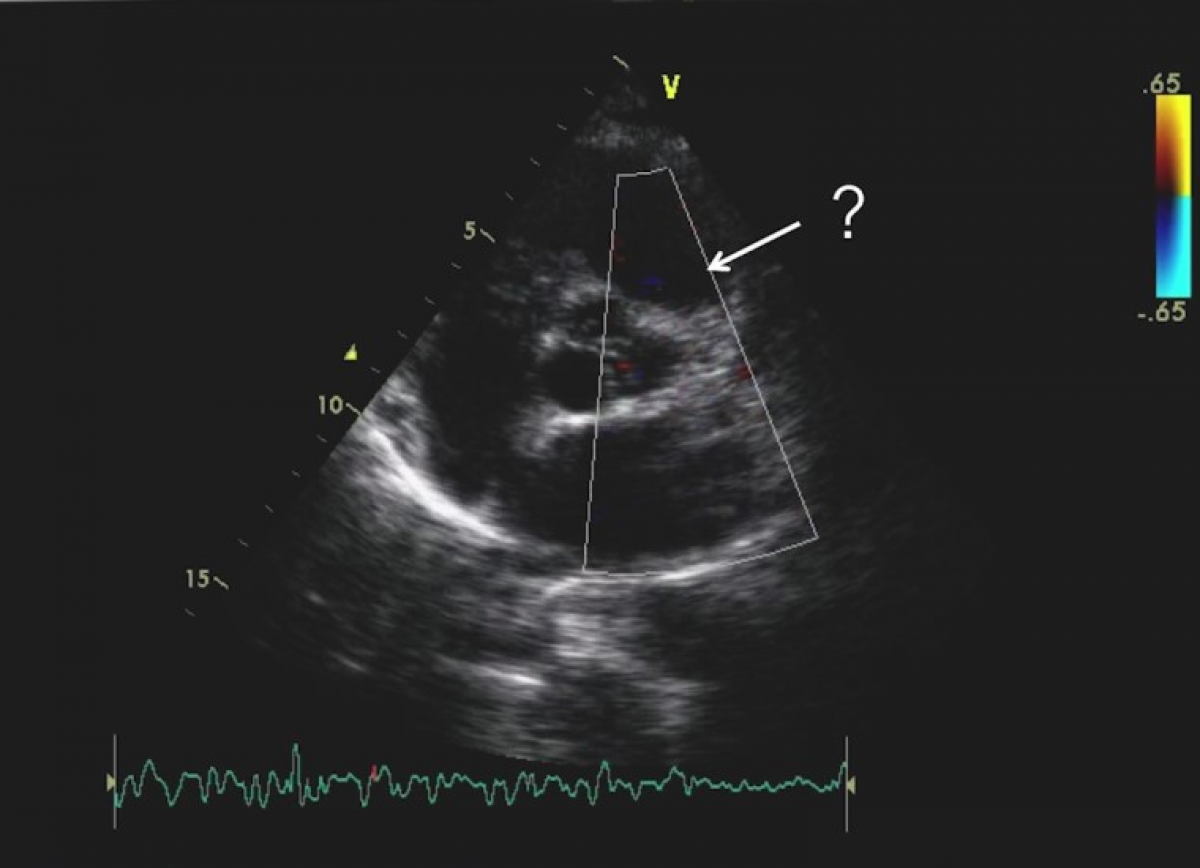

Pacjentka z bólem w klatce piersiowej.

Zespół Bland-White-Garland (ALCAPA)

Echokardiografia przezklatkowa

Ocena ujść tętnic wieńcowych

Obrazowanie kolaterali wieńcowych